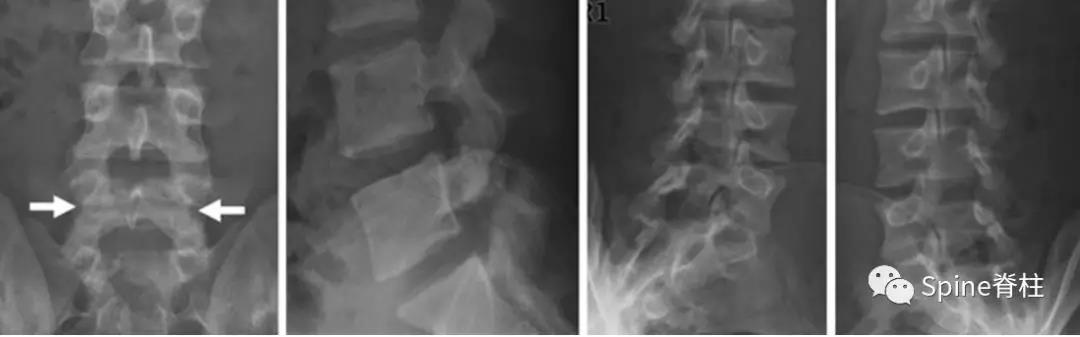

图:起始CT提示L5左侧峡部裂(双箭头),起始CT检查后2个月复查可见出现右侧椎弓根裂(单箭头),4个月复查可见椎弓根裂愈合(单箭头)